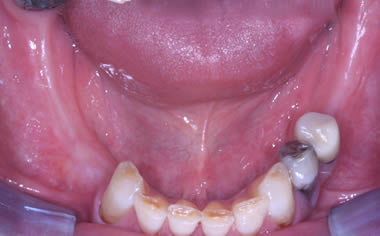

More back teeth replaced by dental implants

Case Five (4 images)